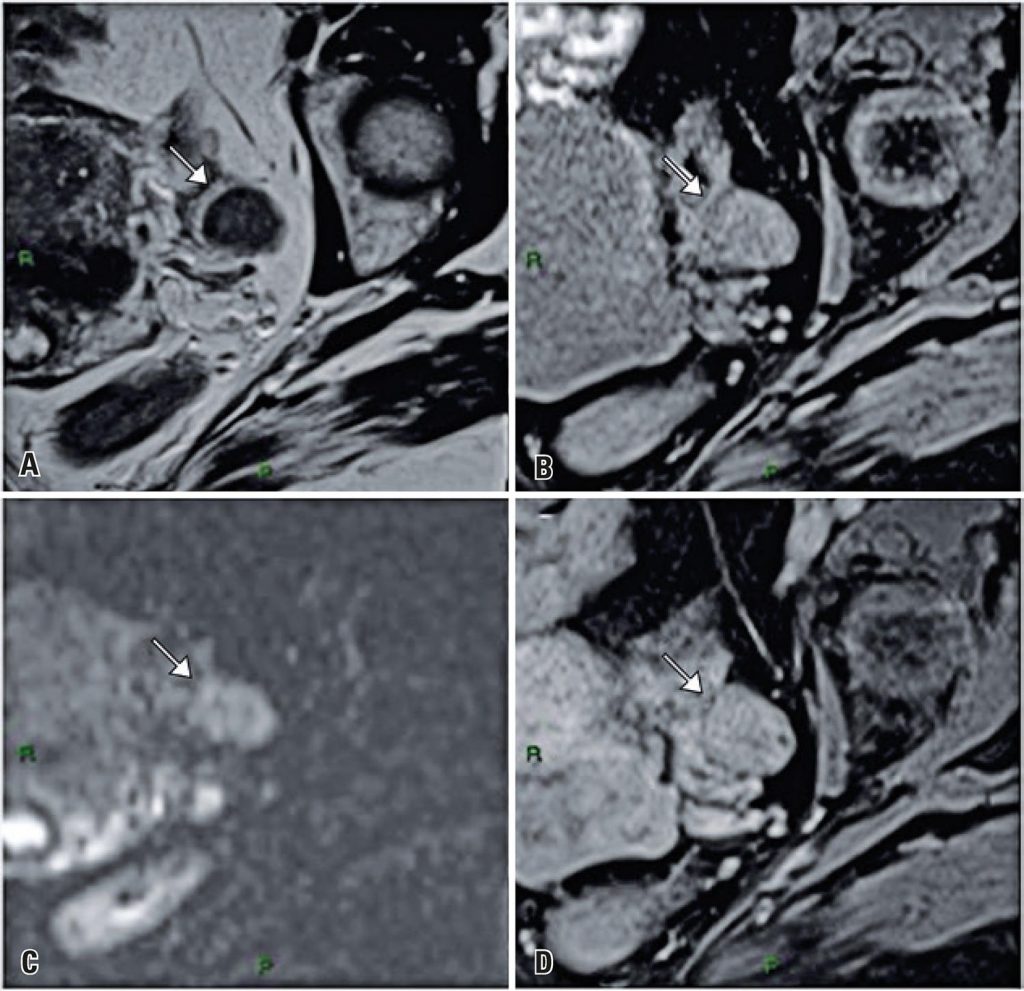

To evaluate whether the presence of a hypointense signal at T2-weighted imaging in a solid ovarian lesion on magnetic resonance imaging is a predictor of stability and benignity.

T2-weighted imaging hypointensity can be considered a predictor of stability in solid ovarian lesions when associated with iso/hypointensity in T1-weighted imaging.